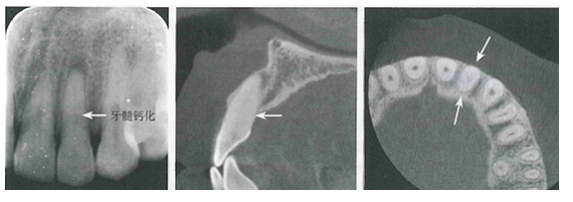

【影像学表现】牙髓钙化X线表现有两种类型,一是局限性,表现为髓石;一是弥散性,表现为髓室及根管钙化。局限性髓石与髓室形状有一定关系。后牙髓石往往表现圆形或卵圆形,大小不一。髓石可游离于髓室内,也可附着于髓室壁。前牙髓室较小,髓石可呈条状或针状充满于髓室及根管内,其周围有线状低密度影像围绕。弥散性牙髓钙化表现为正常髓室及根管影像完全消失,不能辨别出髓腔界限。有的髓腔尚可见,但变得很细,这种情况通常影响牙髓和根管治疗。